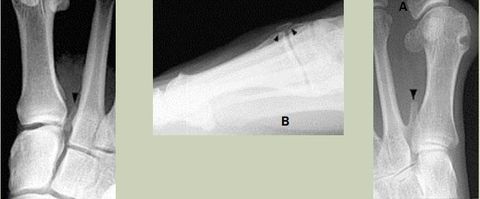

What do the arrows show? | Stress fracture |

Describe what has happened at the shaft of the 3rd met | Exuberant periosteal new bone production. May have resulted if a stress fracture was not treated and the patient continued weight bearing activities. |

What type of fracture is this? | Greenstick fracture (common in paediatric patients) |

Describe what the arrows are showing | Torus fracture of the 1st met. "Buckling" of the proximal one third diaphysis is seen both medially and laterally. Common in paediatric patients |